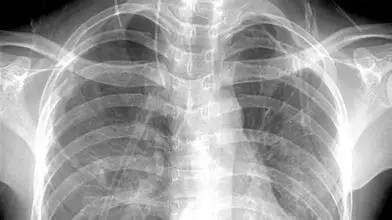

X光:像把面包压扁了看

X光会穿过人体,遇到被遮挡的部位,底片上不会曝光,洗片后这个部位就是白色的。

就像一片面包或一块棉花,看不到里面的纤维纹理,但用手压瘪了会清晰一些。X光最大缺点是受制于深浅组织的影像相互重叠和隐藏,有时需要多次多角度拍摄X光片。

1、外伤骨头——粗看X光片、细看CT

各种外伤,如果怀疑伤到了骨头,优先选择X光照片,检查结果快速易得。若要进一步观察,可以选择CT。超声、核磁对于骨皮髓质等看不大清,一般不选择。

3、胸部——粗看X光片,细看CT

X光胸片可粗略检查心脏、主动脉、肺、胸膜、肋骨等,可以检查有无肺纹理增多、肺部钙化点、主动脉结钙化等。

胸部CT检查显示出的结构更清晰,对胸部病变检出敏感性和显示病变的准确性均优于常规X光胸片,特别是对于早期肺癌确诊有决定性意义。但是CT检查的辐射剂量高于X光。核磁对于肺部疾病的诊断,应用非常有限。